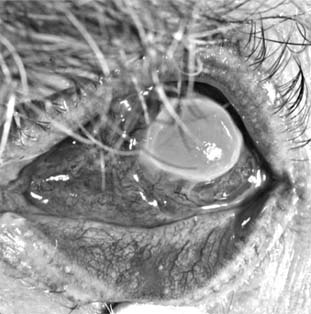

2. MOOREN'S ULCER(Figure 6-8)

The cause of Mooren's ulcer is still unknown, but an autoimmune origin is suspected. It is a marginal ulcer, unilateral in 60-80% of cases and characterized by painful, progressive excavation of the limbus and peripheral cornea that often leads to loss of the eye. It occurs most commonly in old age but does not seem to be related to any of the systemic diseases that most often afflict the aged. It is unresponsive to both antibiotics and corticosteroids. Surgical excision of the limbal conjunctiva in an effort to remove sensitizing substances has recently been advocated. Lamellar tectonic keratoplasty has been used with success in selected cases. Systemic immunosuppressive therapy may be helpful in advanced disease.

Figure 6-8

Figure 6-8: Advanced Mooren's ulcer.